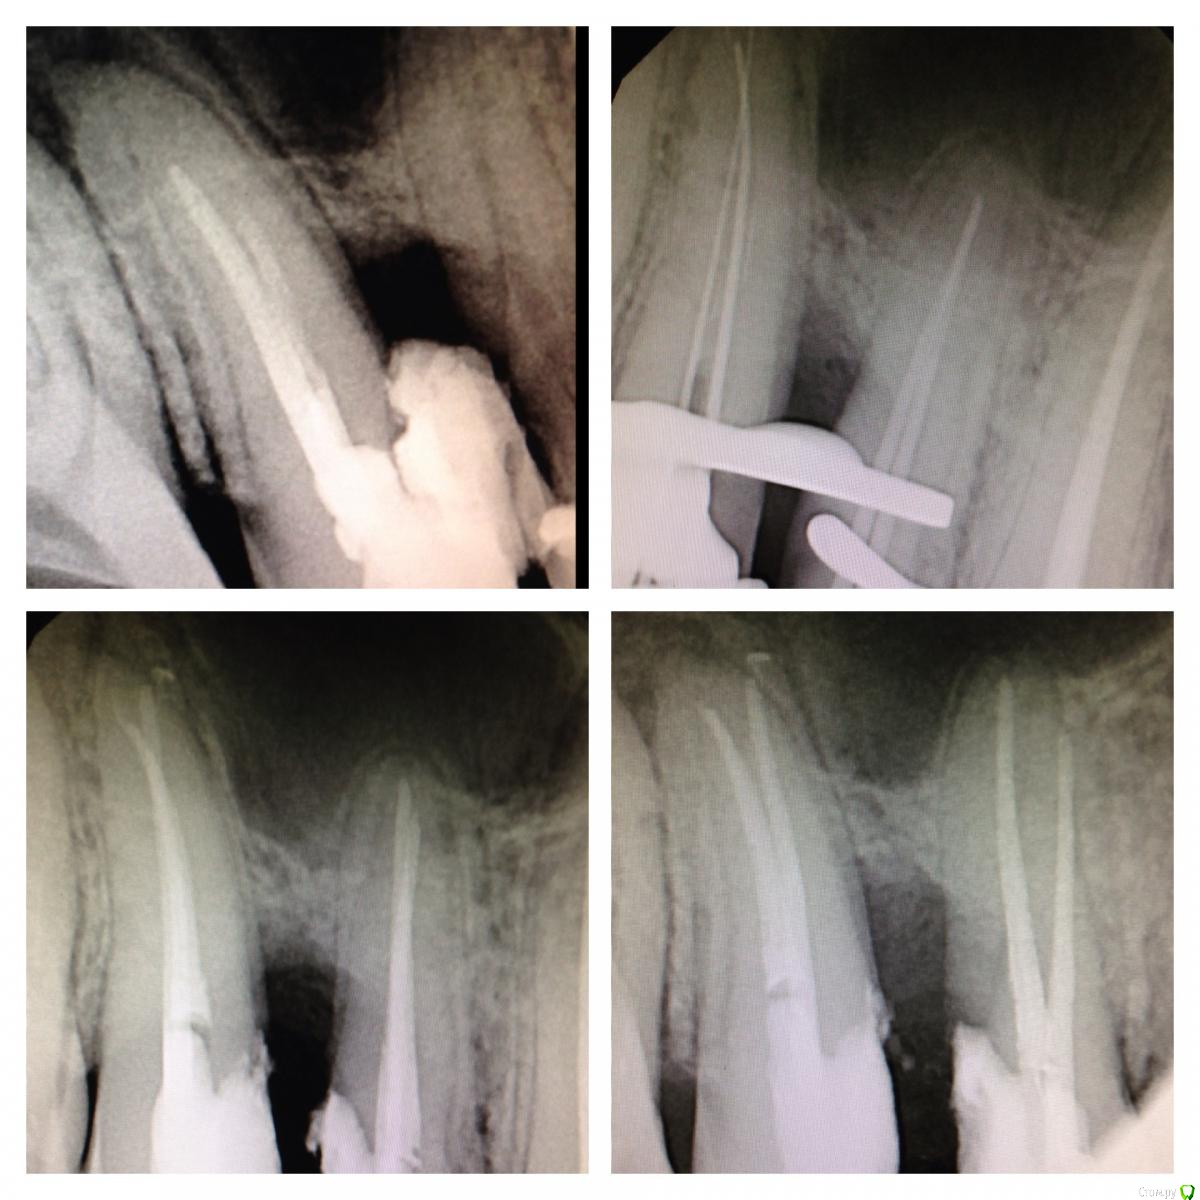

SSTi Опубликовано 15 января, 2015 Автор Поделиться Опубликовано 15 января, 2015 Немножко эндо 24. Резорцин старый. 35.04-45.02. 14-15. Ситуация плохая. 16 тоже под вопросом. Пока попробуем так. Подвижности нет. 14 пульпит ( сначала обработал его ( 35.04. ). 15 асимптоматич. Апикальный периодонтит( его следом обработал 35.04. Кто-то очень умный на половину небного канала засунул цемент). Запаковались. 13- эндометазоновый рай) перелечка метазона. Перед протезированием. На очереди 15. Снимок до на пленке. 3 Ссылка на комментарий

SSTi Опубликовано 19 января, 2015 Автор Поделиться Опубликовано 19 января, 2015 Так. Продолжение. 13 в предыдущем сообщении. Сегодня 15. Цемент. Или что-то подобное. Очень твердое. Изнурил меня зуб. 45 упор. Рд минус 1. 4 Ссылка на комментарий

SSTi Опубликовано 20 января, 2015 Автор Поделиться Опубликовано 20 января, 2015 14-15. 35.04-40.02. Витальные. 4 Ссылка на комментарий

SSTi Опубликовано 21 января, 2015 Автор Поделиться Опубликовано 21 января, 2015 Легкий и приятный кейс. 46. Витальное эндо. Медиальные 35.04, дистальные 40.04. Дистальных 2. В конце инструментации ушла перегородка и они объединились в 1 протяженный щелевидный канал. Латералка. 7 Ссылка на комментарий

SSTi Опубликовано 22 января, 2015 Автор Поделиться Опубликовано 22 января, 2015 Вот нашел. Может выкладывал уже. Но вроде нет. Любимые нижние премолярки) 5 Ссылка на комментарий

SSTi Опубликовано 4 февраля, 2015 Автор Поделиться Опубликовано 4 февраля, 2015 45. Многострадальный. 1- изоляция. Преп. Извлечения штифта. 40.04-70.02. Гх-эдта-гх уз - эдта - кальций. ЦемилайтПериостотомия2- изоляция- преп- эдта- гх уз - аспирация - перекись - хг. ОбтурацияЛатералка с модификацией) 4 1 Ссылка на комментарий